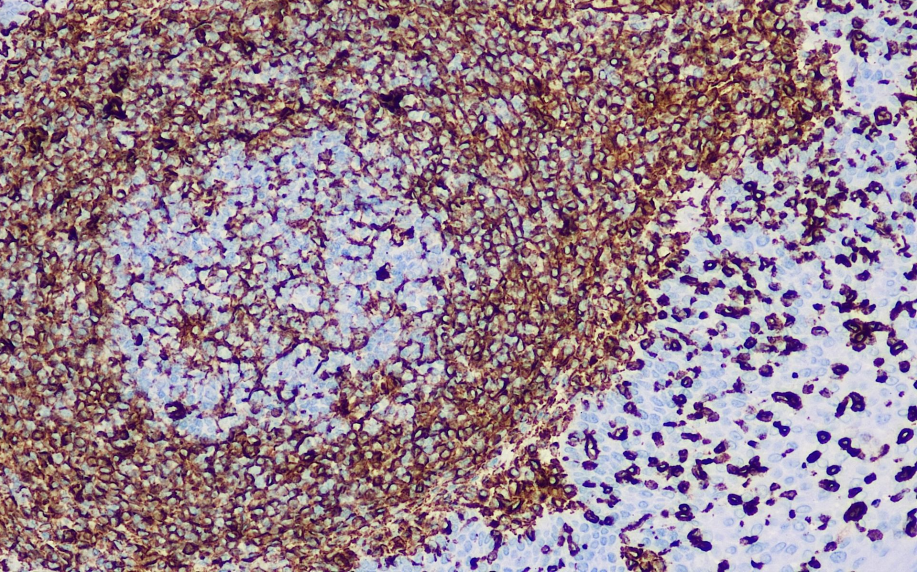

Positive control: tonsils

Wave protein is a common member of the intermediate filament protein family and a major component of the cellular cytoskeletal structure. It is expressed in the development and differentiation of various mesenchymal cells and cell types derived from the mesoderm. Wave protein plays a role in maintaining cellular integrity and cytoskeletal stability. Similar to all intermediate filament proteins, the reorganization of vimentin occurs at the same stage of the cell cycle and cellular signaling pathways through site-specific phosphorylation (serine or threonine residues). In particular, phosphorylation at Ser25, Ser38, Ser50, Ser65, and Ser72 by p21-activated kinase (PAK) induces vimentin-specific reorganization. During cytokinesis, p53 is regulated by Rho kinase (ROCK) and Aurora B through phosphorylation at Ser38 and Ser72. p53 serves as a relatively specific reference marker for mesenchymal cells and their derived tumors.

Vimentin antibody reagents can specifically bind to Vimentin molecular antigens. Immunohistochemistry kits containing Vimentin antibody reagents are suitable for the auxiliary diagnosis of tumors originating from mesenchymal tissues (such as sarcomas, carcinosarcomas, and melanomas).